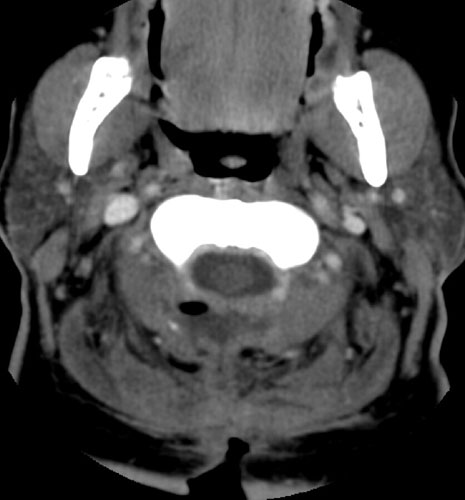

Contrast enhanced axial CT scan  demonstrates unroofing of the spinal canal from the C2 to the C7 with bilateral laminectomies and removal of the spinous processes. There is a fluid collection without significant rim enhancement in the post surgical bed at the C2 level, posterior to the spinal canal. Within this, there is some air. The fluid collection appears to extend inferiorly to the C3 level, and then a small slit of fluid continues inferiorly to the C5 - 6 level (not shown), where it appears to communicate with the midline incision .